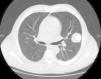

En la nueva TAC de tórax de control a los 3 meses (fig. 1) se observó un aumento de tamaño de la masa en el LSI (4,9×4,1cm). Se decidió, entonces, resección quirúrgica de la masa pulmonar. El diagnóstico anatomopatológico fue de condrosarcoma metastásico. Se revisaron las biopsias previas de la tumoración de paladar intervenida hace 12 años, concluyendo que se trataba de un tumor mixto con un doble componente epitelial y mesenquimal. El componente epitelial era escaso y benigno. El componente maligno correspondía a un condrosarcoma mesenquimal.